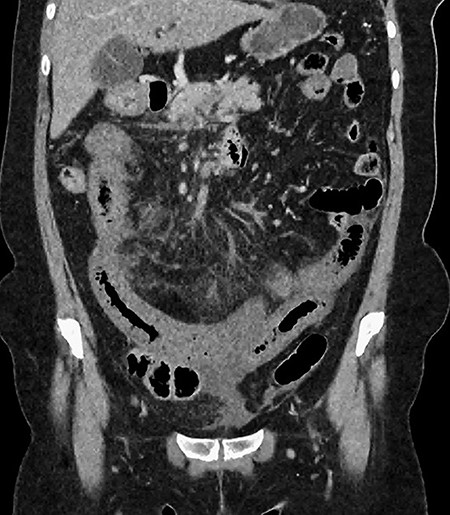

A 61-year-old female presented to a regional hospital with a 3-week history of intermittent diarrhoea, vomiting and generalized abdominal pain. She had a diffusely tender abdomen but was not peritonitic, and was shocked with a heart rate of 110 beats per minute, blood pressure of 89/45 mmHg and was peripherally cool. Her blood tests revealed a lactate of 7.2 mmol/L, which worsened to 7.8 mmol/L during resuscitation with intravenous fluids, and white cell count was 30.9 × 109/L, with an international normalized ratio (INR) of 1.4. She had an acute kidney injury with a creatinine of 119μmol/L and estimated glomerular filtration rate (eGFR) of 43 mL/min/1.73m2. Computed tomography (CT) revealed extensive thickened loops of non-enhancing small bowel with pneumatosis, moderate free fluid and a large splenic infarction. There was extensive thrombosis of the splenic vein and superior mesenteric vein extending into the portal vein to the level of the porta hepatis. Her background history included factor V Leiden and protein S deficiency, for which she had been non-compliant with warfarin during this illness. She had no surgical history (Figs. 1–5).

CT showing multiple thick-walled, non-enhancing loops of small bowel.

CT showing complete occlusion of the portal vein at the level of the porta hepatis.

CT showing an area of splenic infarction due to venous ischaemia.